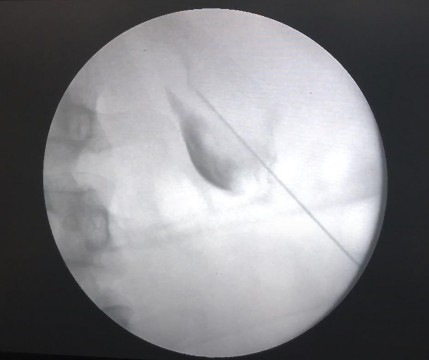

Hình 2.21. Nong tạo đường hầm dưới kiểm soát của màn hình tăng sáng

(Nguồn: chụp tại Bệnh Viện Trường Đại Học Y - Dược Huế)

Tiếp theo luồn dây dẫn ái nước 0.038” (Radiofocus, Terumo, Tokyo, Japan) vào niệu quản, nong đường hầm bằng Dilator 8F.